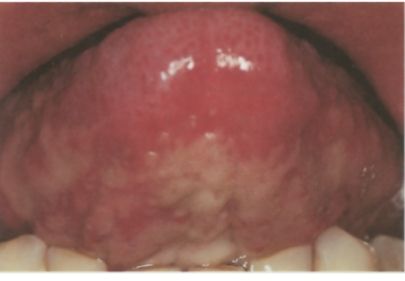

Desquamatin bullous inflammation of oral mucosa in a patient of the controll group

Condition during radiotherapy with desquamating bullous inflammation of the oral mucosa in a patient of the control group